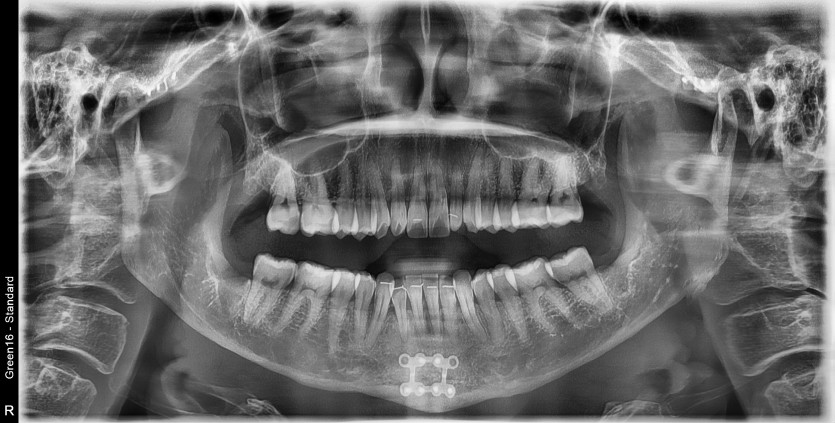

#18,28,38,48 사랑니 발치

구강 외과 전문의가 당일 발치했습니다.